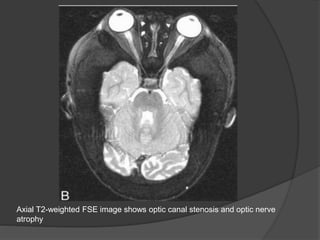

Axial T2-weighted FSE image shows optic canal stenosis and optic nerve

atrophy

Axial T2-weighted FSEimage shows optic canal stenosis and optic nerve atrophy